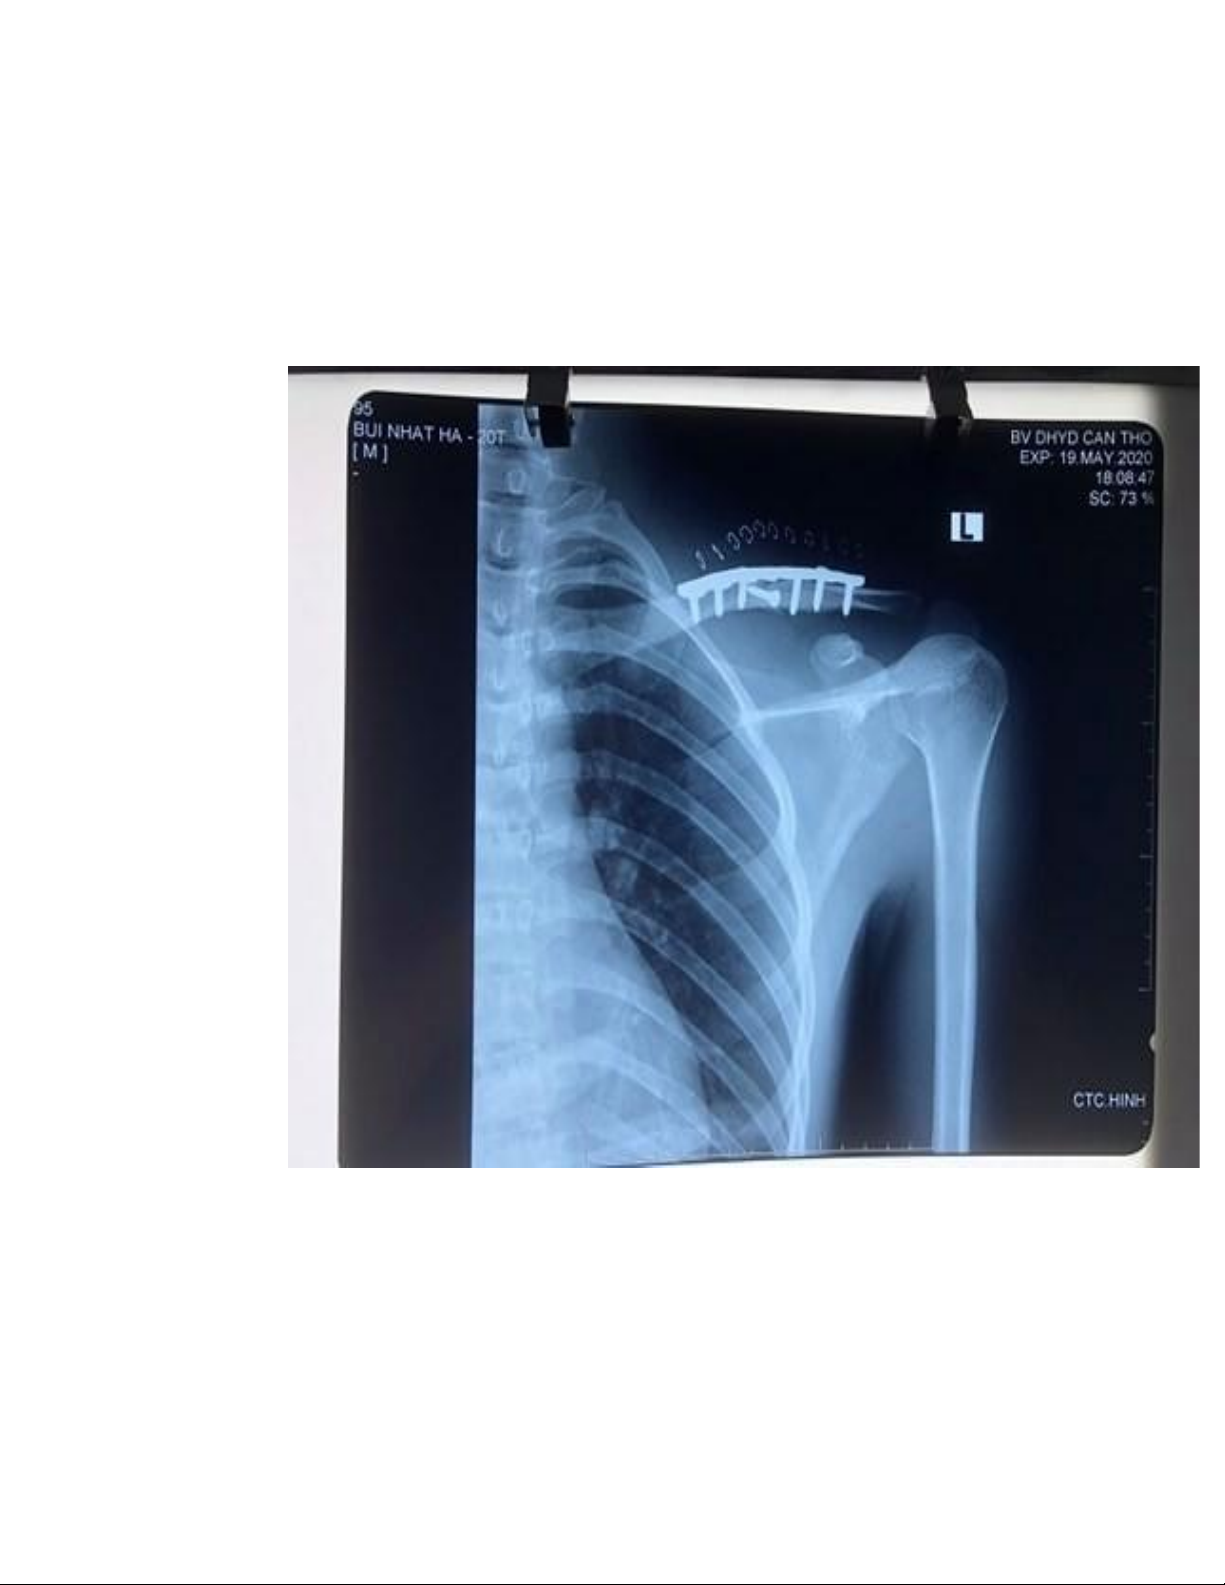

Xquang sau phẫu thuật: gãy 1/3 giữa xương đòn (T) đã bắt nẹp 8 lỗ

( 3 lỗ đầu gần và 3 lỗ đầu xa) + 1 lag screw